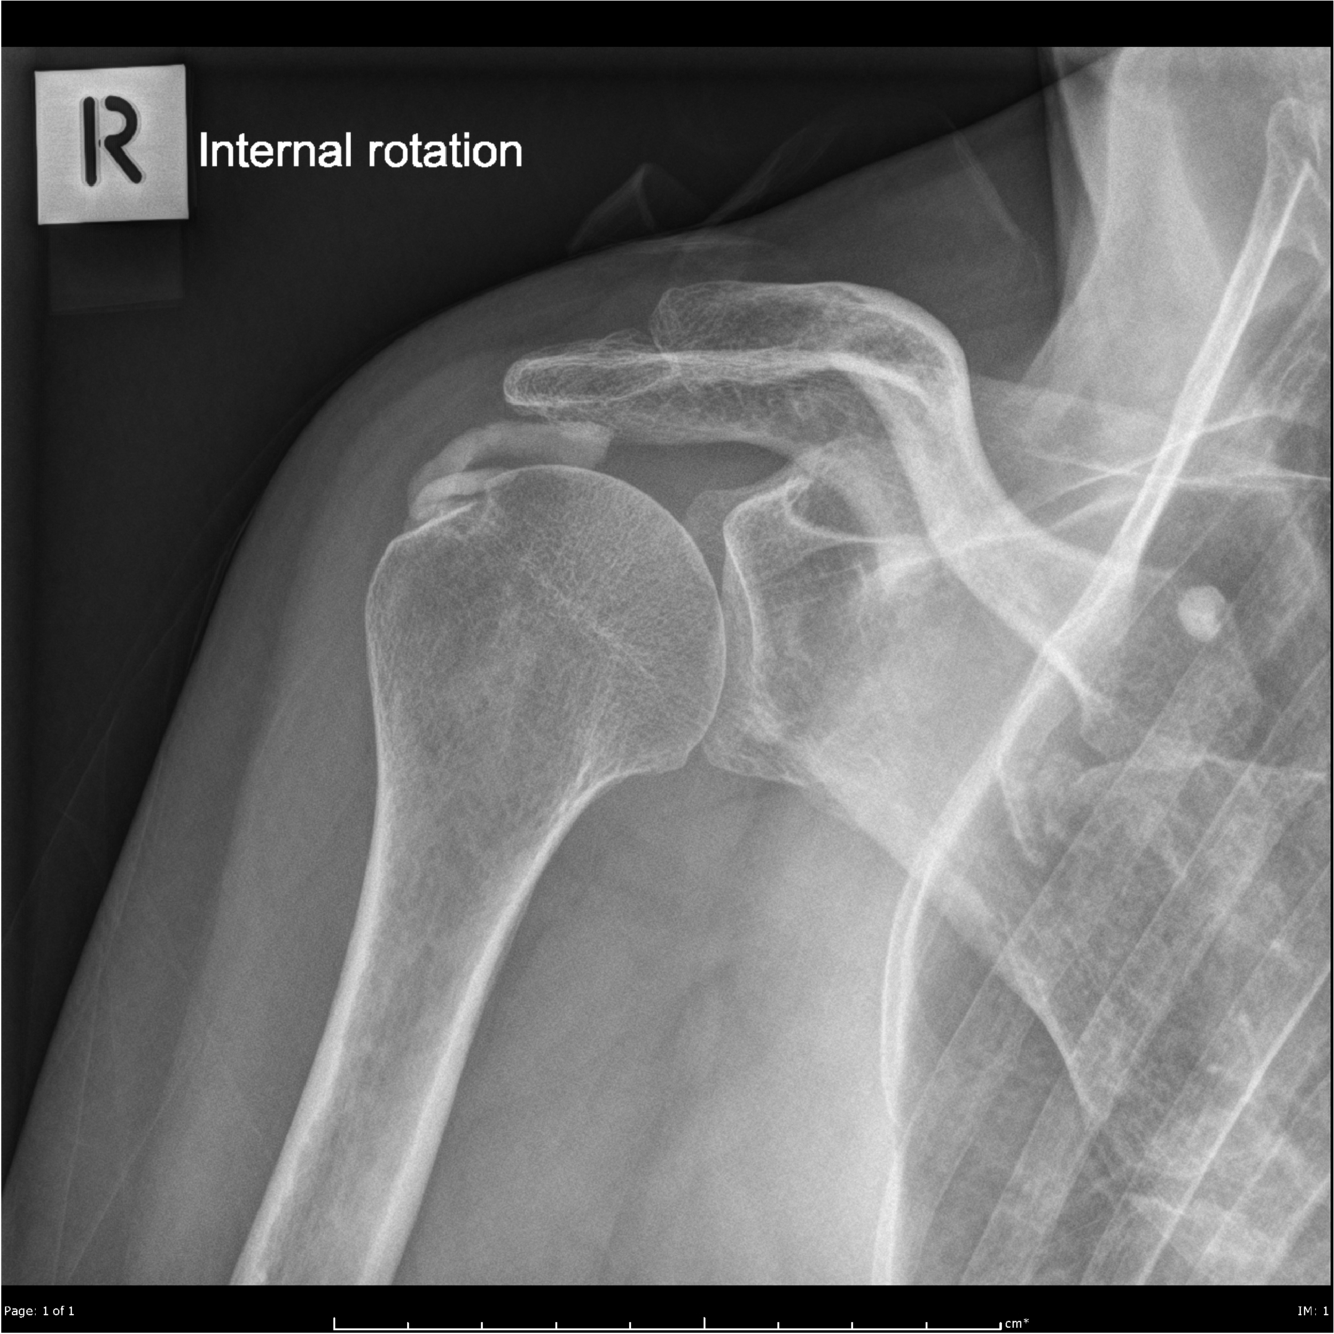

Hydroxyapatite deposition disease

Dr Mohamed Saber and Dr Prashant Mudgal et al.

Hydroxyapatite crystal deposition disease (HADD) is a disease of uncertain aetiology characterised by periarticular and intra-articular deposition of hydroxyapatite (HA) crystals.

The shoulder is the most frequently involved site with classic calcific tendinitis presentation.

Plain radiograph

It appears as homogeneous, round-to-ovoid calcification in the soft tissue with well-defined or ill-defined margins. The most characteristic lesions are seen in the shoulder with supraspinatus and biceps tendon involvement, adjacent to the greater tubercle and the glenoid tubercle, respectively, where these tendons attach.

Deposits within the infraspinatus and teres minor tendons are not uncommon and can be seen adjacent to the greater tuberosity on internal rotation or axillary views 1.